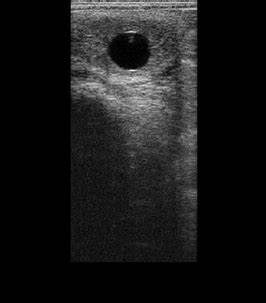

La commande de la semence est alors effectuée par le vétérinaire inséminateur, en fonction de l'évolution échographique des follicules.